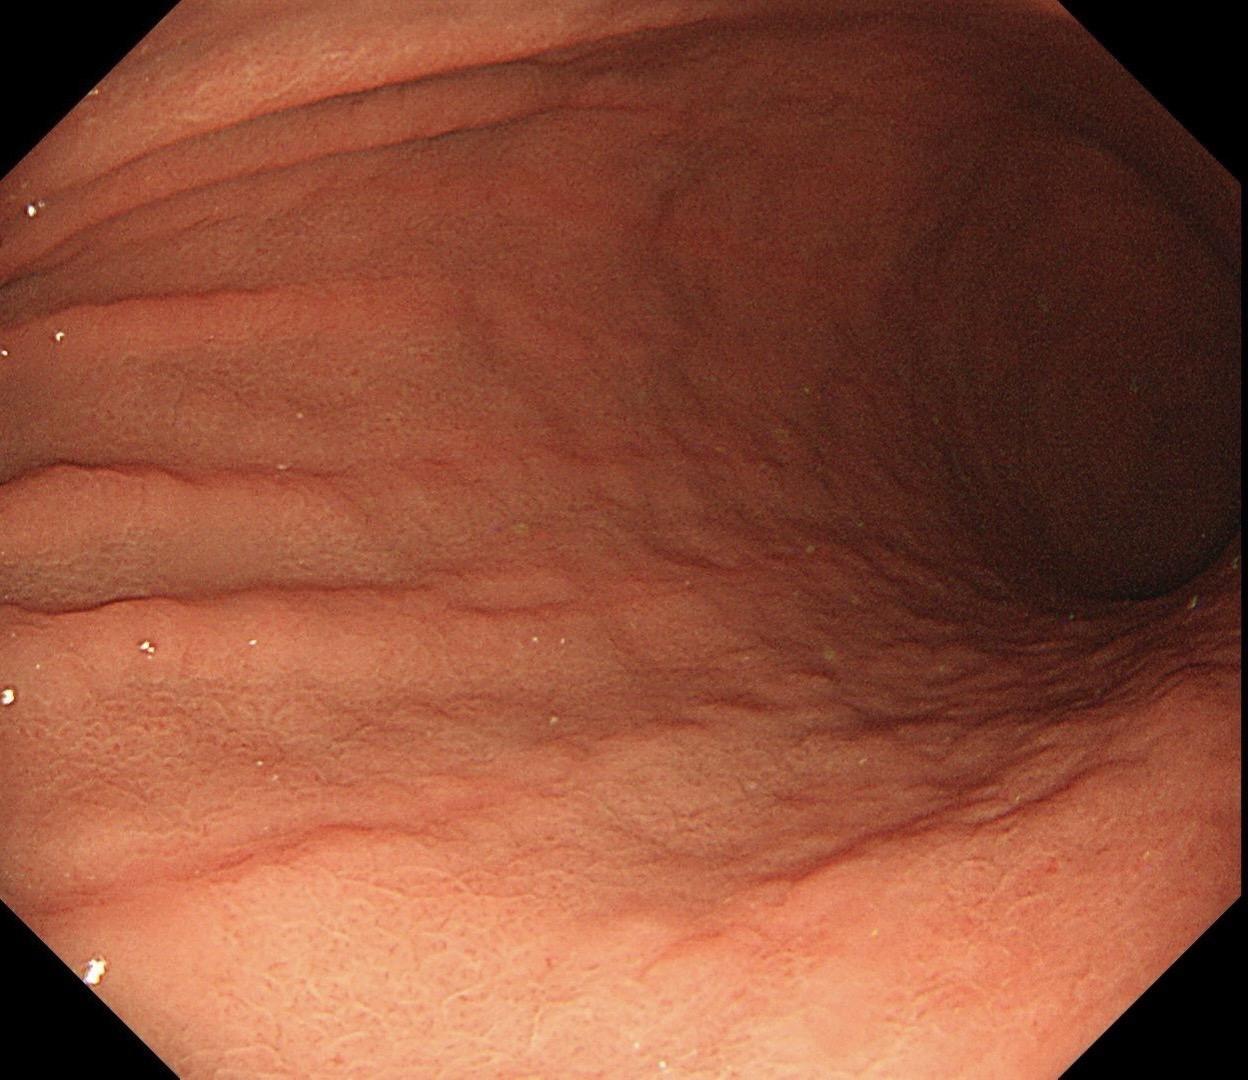

男,40岁,胃双发褪色调病变。慢性胃炎复查,3年前胃镜未见异常,Hp阳性背景,萎缩不明显,胃体下部大弯见一褪色调病变,浅凹陷,5mm左右,换用放大内镜观察,表面结构缺失,血管异型明显,未分化可能性大……胃窦后壁见一白斑,无高度差,NBI浅茶色,放大草草看了下,似有边界,IP增宽,活检待病理……小哥哥胖得几乎没脖子,腹式呼吸太明显~😖